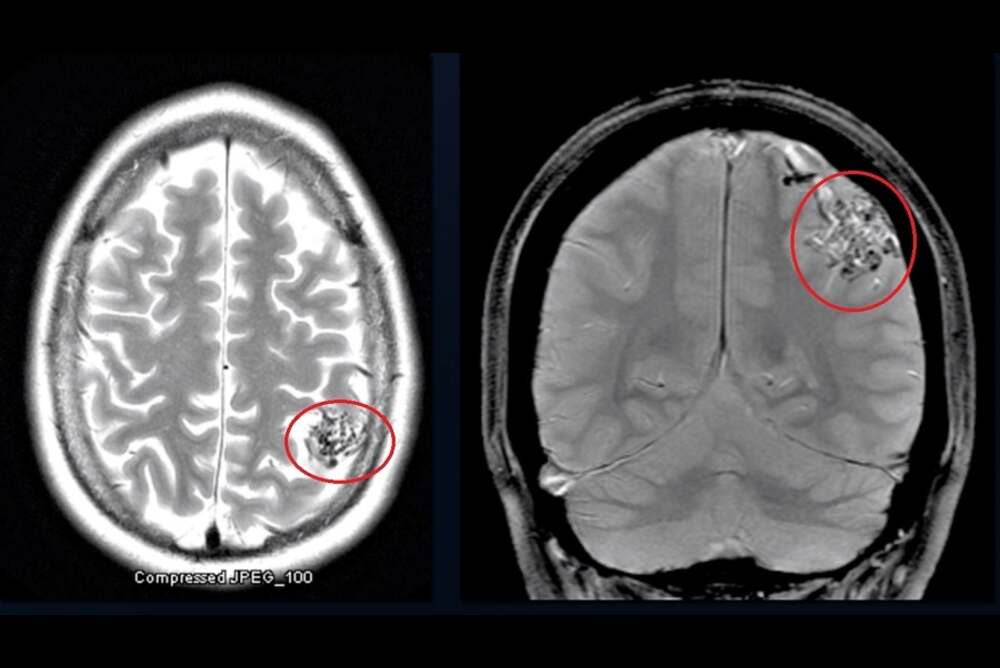

There is no evidence of cause of this condition that is not a result of environmental or lifestyle factors. Thus, the diagnosis is crucial and heavily depends on the area that is AVM Radiology. Modern imaging techniques such as MRI as well as CT angiography are employed to precisely determine the size of the malformation and location as well as pattern of flow. The precise radiological assessment is vital for precise guidance in subsequent treatment plans and to ensure a safe treatment strategy.

The brain AVMs can be classified by their place of origin and blood supply, which determines the treatment plan. The most common kinds are:

- Pial AVM is situated on the top of the brain. It is supplied via branches of the internal carotid artery (ICA)

- Dural AVM is located inside the tough outer layer of the brain (the dura) and is supplied via some branches from the external carotid artery (ECA)

- Mixed AVM: Provided via branches of both the ICA and ECA